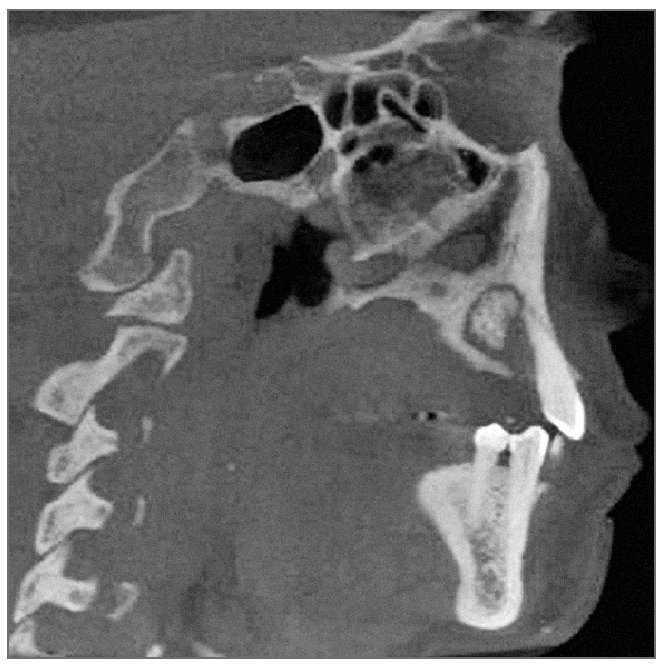

Las radiografías periapicales de la región, tomadas en el momento de la biopsia (fig. 3), revelaron una lesión de densidad mixta bien delimitada en el área de los premolares superiores izquierdos extraídos que se extendía unos 2 cm en sentido anteroposterior. La lesión se extendía desde la cresta del reborde alveolar hasta el suelo del seno maxilar. Los alvéolos de extracción se discernían claramente.

Figura 3. Radiografía periapical del primer premolar superior izquierdo después de la extracción del segundo premolar.